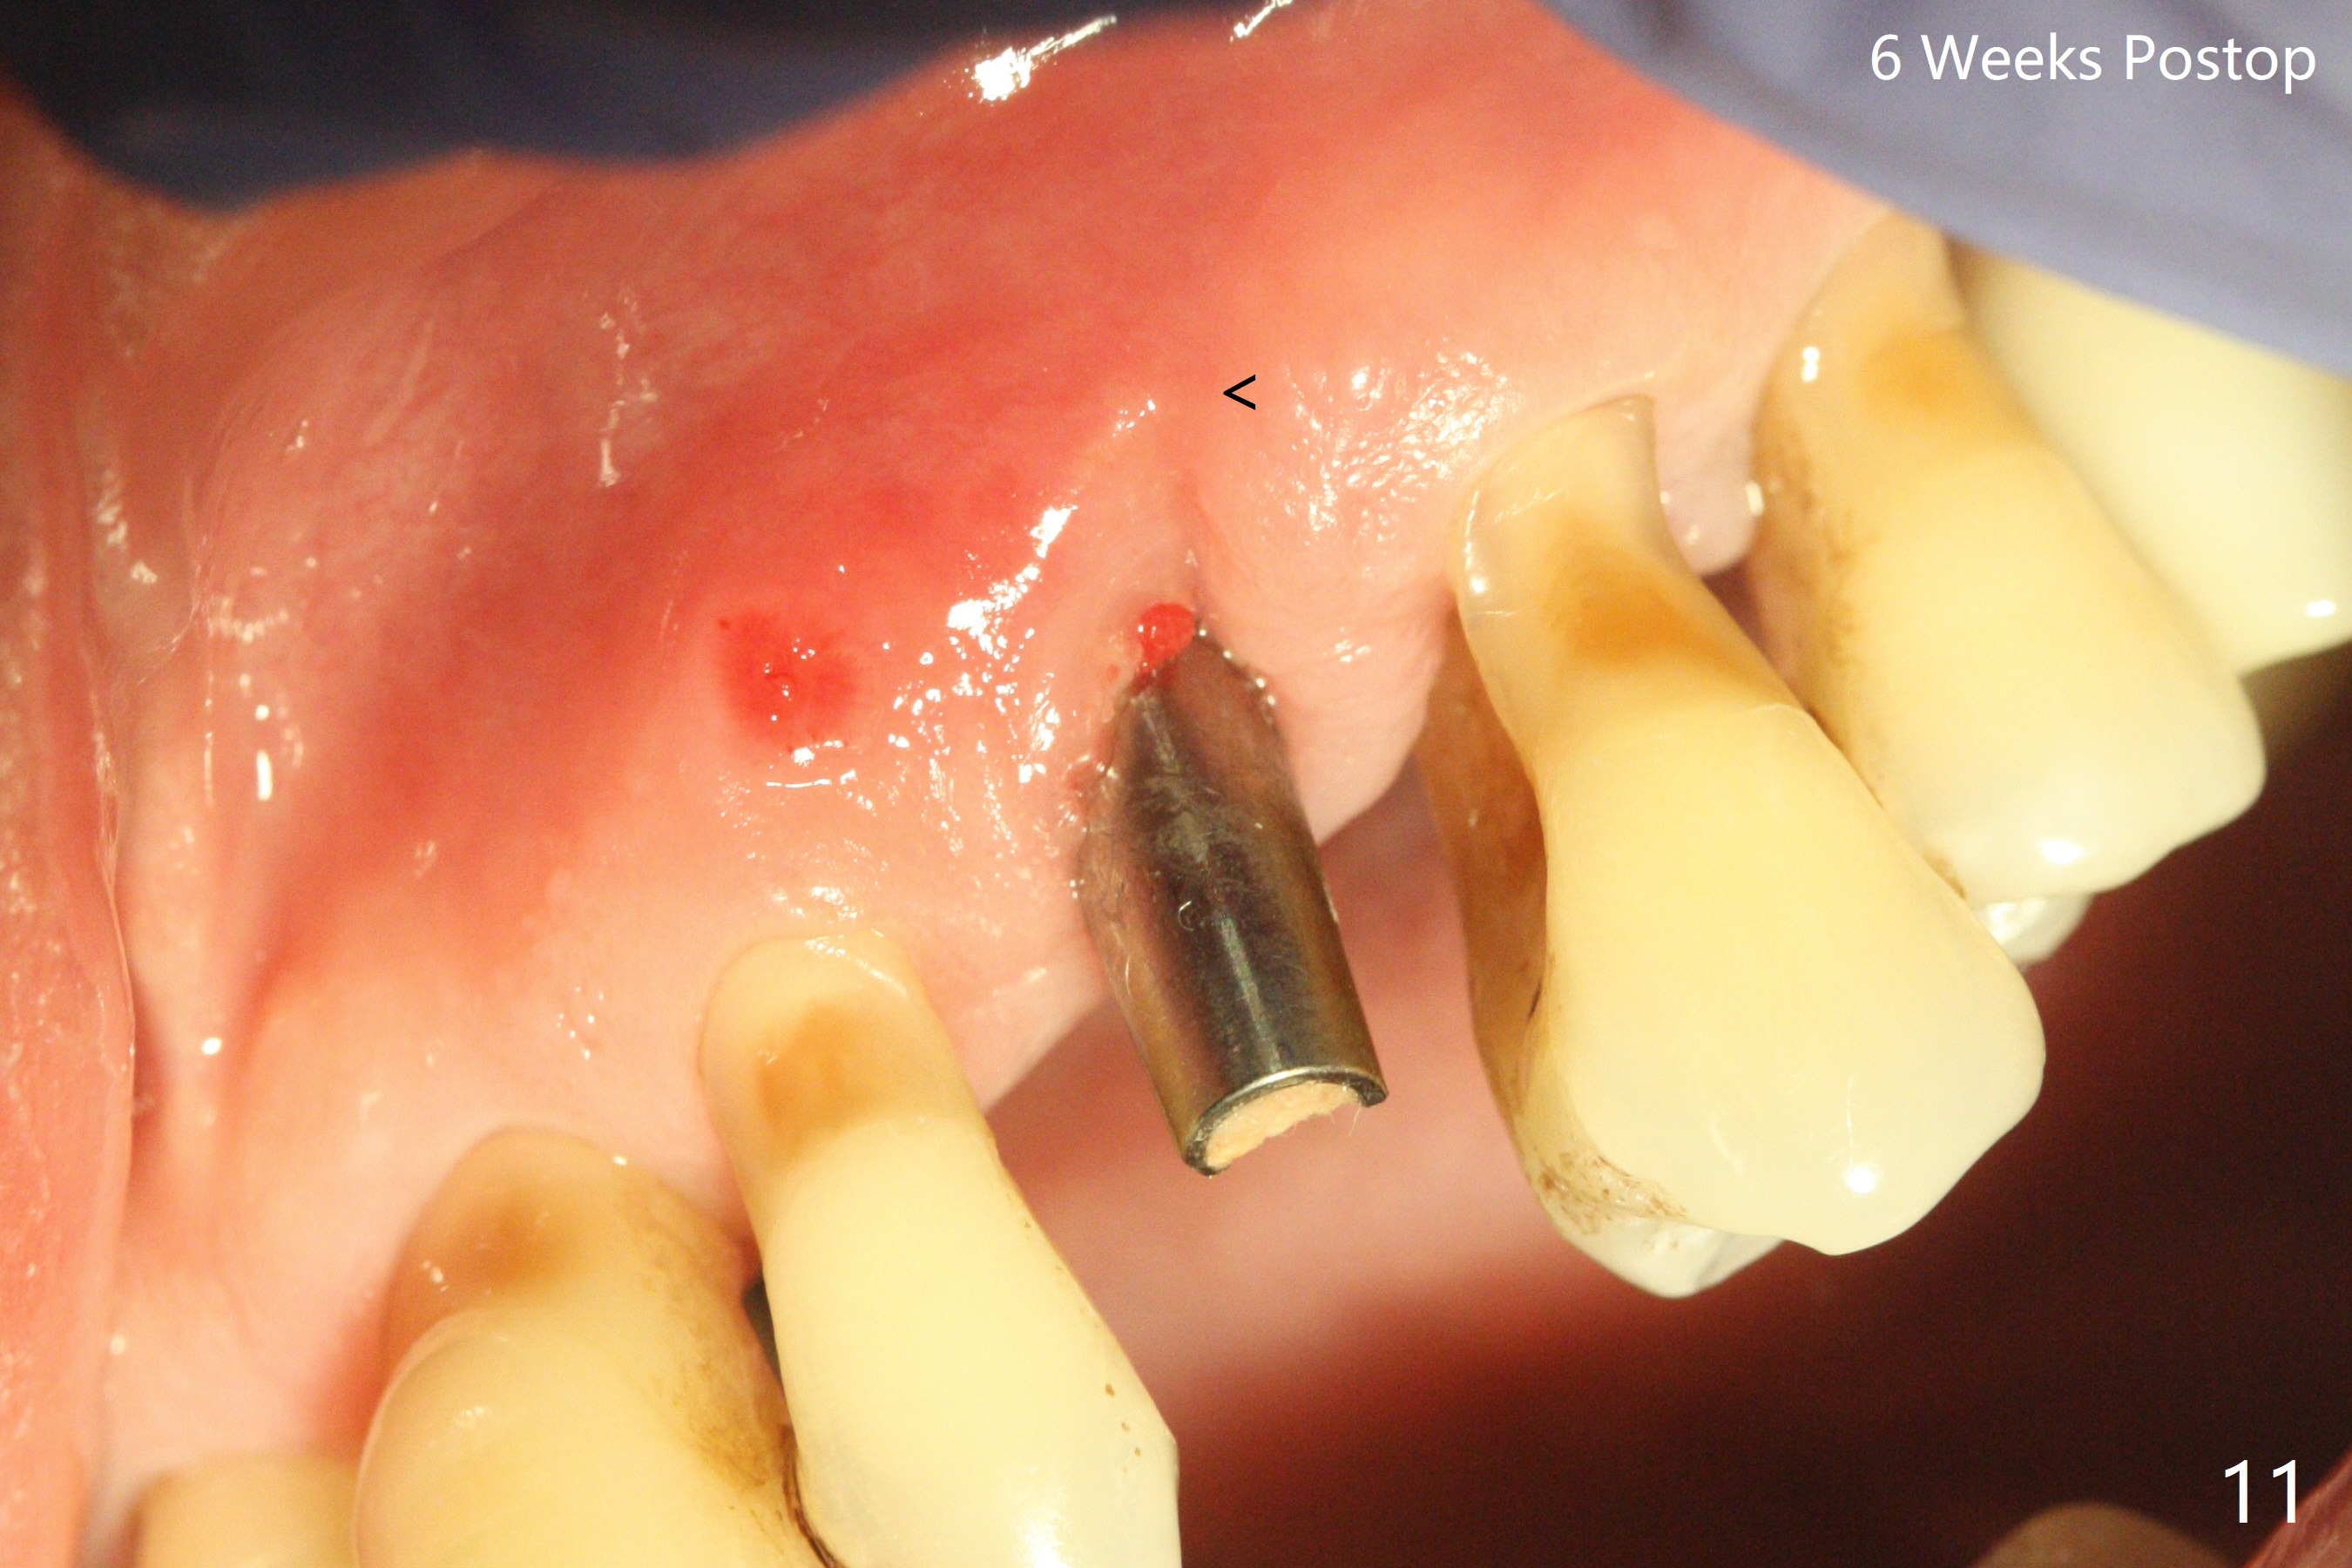

A 62-year-old man with generalized chronic periodontitis returns with chief complaint of loose tooth at #11 (Fig.1). Although a buccal fistula (Fig.1 <) is closer to #12 than to #11, percussion is more severe at #11 than 12. The buccal plate of #11 is missing, but it is possible to place a narrow immediate implant because of the wide alveolus (Fig.2). Since the gingiva is ~ 10 mm long, a mill abutment is to be used (Fig.3,5). In fact the fistula communicates with #11 extraction socket. After debridement, osteotomy is initiated (Fig.4) for a 3.8x10 mm implant ~ 35 Ncm, followed by seating a 4.5x2 mm mill abutment (Fig.5). Abundant sticky bone is placed in the remaining socket (for buccal plate reconstruction) and against the root surface of the neighboring teeth (Fig. 6 * (#10,12)). Finally 2 pieces of PRF membranes are utilized to facilitate repair of the buccal soft tissue defect (Fig.7 *). The root prominence of the canine seems to be maintained by the bone graft (Fig.8 C). Acrylic dressing holding the PRF membranes in place remains in situ with the healthy gingiva buccal (Fig.9) and palatal (Fig.10) 11 days postop. Note the acrylic locking into the undercuts of the neighboring teeth (*). 经过一段摸索发现离心每分钟1500转5分钟后,抽取上清液,接着再离心10分钟剩余上清液就形成血小板块,压制后便是血小板膜,后者似乎有助于软组织愈合,而上清液用来制备骨块,帮助硬组织生长。利用这个原则讨论以下病例治疗。The gingival margin gains ~ 5 mm 6 weeks postop when the acrylic dressing is removed (Fig.11,12 (<: previous one), as compared to Fig.7,8). 治疗结束时尖牙牙龈缘高于第一双尖牙(图七,八),六个星期后,尖牙牙龈缘却低于双尖牙(图十一,十二(箭头:原始牙龈缘))。术后2.5,4.5月基台周围牙龈似乎能与钛合金附着,防止细菌进入深部植体(图十三,十四)。临时牙冠脱落多次,可能与mill abutment太光滑有关,所以颊侧,舌侧磨成平面(图十四)。取模时好像不必取出基台清洗(仿佛没有炎症),原位用树脂延长基台。术后5个月CT显示颊侧骨板再生(图十六-十八)。取模时并没有用树脂加长基台;粘固时,牙冠颜色理想,但是照片中并不是如此(图十九,二十),颊侧骨板没有塌陷。术后11个月基台颊侧骨板没有萎缩(图二十一:B);3d图像:骨壁完全形成(图十六对比:部分形成)。密度也增高(图二十二:B),与术后五个月比较(图十七)。术后十一个月,粘固后五个月角化龈存在(图二十三),牙冠颈部有金属颜色透出,是因为二段式基台太粗了(最细4.5毫米),可以请实验室在牙冠内部涂opaque material而减轻。